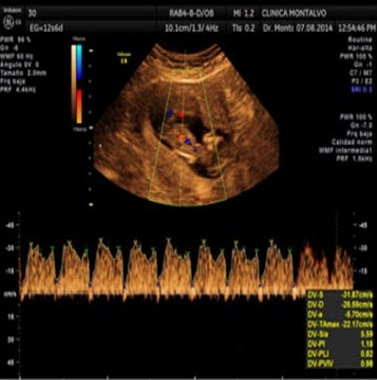

Ecografía Obstétrica

Ecografía 3D y 4D